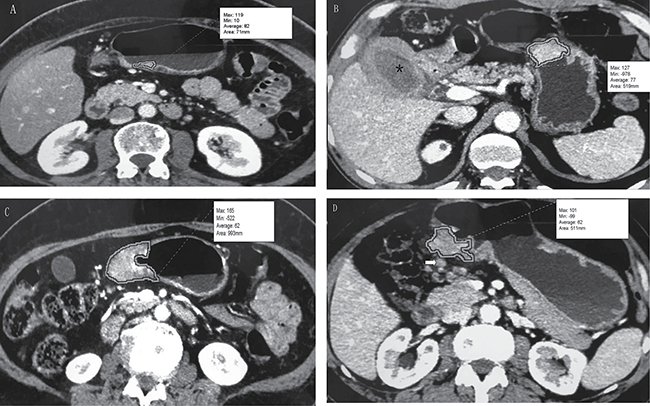

GTV was measured at a window width of 380 HU and window level of 50 HU. The portal venous phase was used for GTV measurement. GTV was calculated by multiplying the sum of all the tumor areas by the section thickness according to a previous report [23, 34, 37]. For delineation of tumor area, we regarded the gastric wall as abnormal when its thickness was ≥ 5 mm on transverse imaging with the stomach distended [19]. Tumor area was manually outlined on each axial enhanced CT image (Figure 3). Sometimes the accurate manually delineation of tumor area is difficult because the tumor may locate on oblique plane on axial CT images. Therefore, coronal or sagittal reconstruction images were obtained on the General Electric Advantage Workstation. The reviewers were given the option to use coronal or sagittal reconstructed images to determine the tumor area when the tumor may locate on oblique plane on axial CT images.

Figure 3: Tumor volume measurement on MDCT. (A) T1 stage gastric adenocarcinoma on the gastric angle in a 58-year-old man. Tumor area is manually drawn along margin of tumor, and value of this area (71 mm) is automatically derived by software together with minimal, maximal, and average CT attenuation (in Hounsfeld units). (B) T2 stage gastric adenocarcinoma on the gastric body and xanthogranulomatous cholecystitis (*) in a 55-year-old man. The tumor had an area of 519 mm. (C) T3 stage gastric adenocarcinoma on the gastric antrum in a 48-year-old man. The tumor had an area of 993 mm. (D) T4a stage gastric adenocarcinoma on the gastric antrum in a 67-year-old man. The tumor had an area of 511 mm. Lymph node metastasis was found adjacent to the tumor (arrow).

Tumor areas were automatically derived by the software. This previous process and analysis were repeated for each contiguous transverse level until the entire tumor had been covered, and the values of each contiguous transverse level were then summed to calculate the GTV. The time required to perform the measurements and calculation of GTV was approximately 200 seconds on average (range, 100 to 350 seconds).